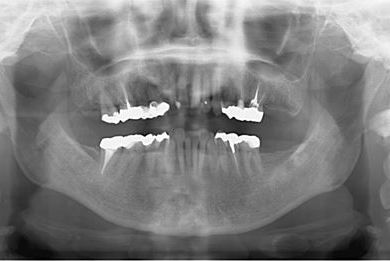

治療前

• 治療前